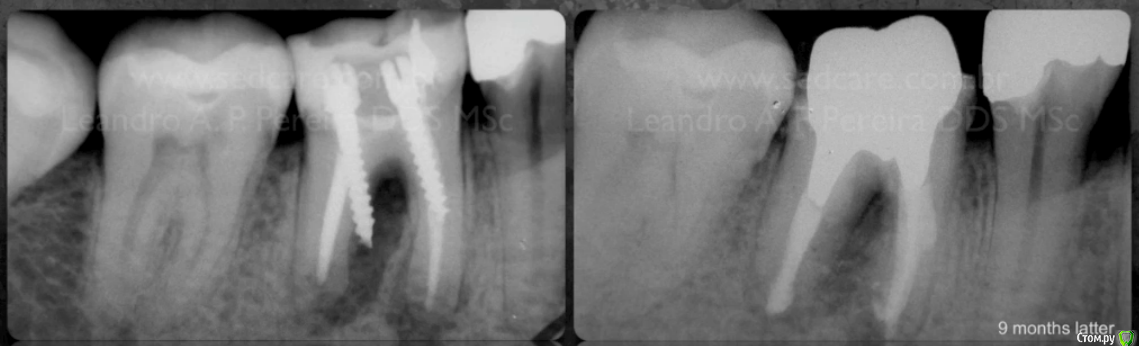

Hishnica Опубликовано 21 ноября, 2015 Поделиться Опубликовано 21 ноября, 2015 Здравствуйте, уважаемые доктора! Была у стоматолога сегодня, зуб-нижняя левая шестерка, восстановлен (наращена пломба), отвалился кусочек пломбы, хотела его восстановить снова, сделали снимок. Врач говорит, что надо удалять. А я не могу решиться на удаление зуба. Подскажите, как лучше, и что это за дырка между корнями? Мне врач ничего не объяснил(((Хижняк_Дарья_Сергеевна_21112015_092353.bmpХижняк_Дарья_Сергеевна_21112015_092411.bmp Ссылка на комментарий

anvladd Опубликовано 21 ноября, 2015 Поделиться Опубликовано 21 ноября, 2015 Корень перфорирован,удалять! Ссылка на комментарий

anvladd Опубликовано 22 ноября, 2015 Поделиться Опубликовано 22 ноября, 2015 попробуйте обратиться к доктору-спасателю с микроскопом Снимок экрана 2015-04-04 в 17.49.07.pngвсе равно скоро крякнется данный зуб! Ссылка на комментарий